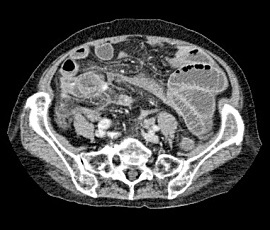

右下腹部痛にて受診。精査の結果、急性虫垂炎、汎発性腹膜炎と診断。手術(腹腔鏡下回盲部切除術、腹腔内ドレナージ術)を施行した。

CT画像